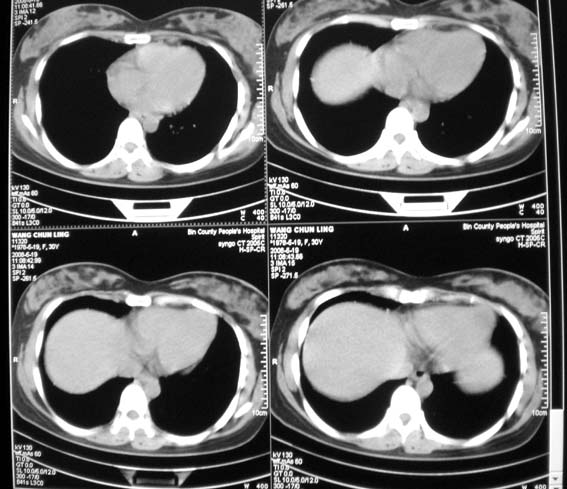

女,30岁,怀孕后3个月,拍片时肺结核,抗结核治疗4个月复查。

前段支气管通畅,但尖后段支气管闭塞,建议支纤镜除外肺癌,有原片吗,对比一下了。

结核.前段支气管通畅,但尖后段支气管闭塞,建议支纤镜除外肺癌

纵隔淋巴结肿大,见意出外占位